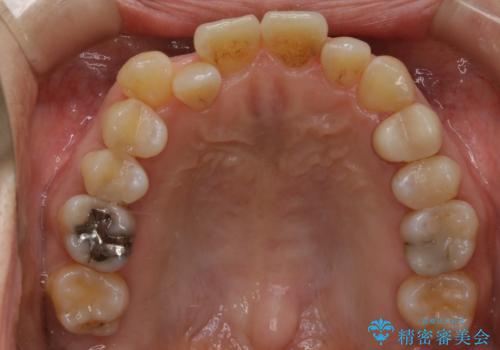

- 右上の2番目の歯が内側に入っているのと、下の前歯のがたつきが気になるとご相談にいらした方です。

上下左右の歯を後ろに動かして歯を並べるスペースを確保し、内側に入っていた歯を綺麗に並べ、前歯の中心もお顔の中心に合うようにしました。

矯正用アンカースクリューを埋入し、上下左右の歯を後ろに動かすことで歯を並べるスペースを作りました。

元々内側に倒れていた右下の奥歯は、ゴムかけを追加で行っていただくことによりしっかり起こすことが出来ました。

歯並びが綺麗になったことでモチベーションが上がり、銀歯からセラミックへのやり替えも行っております。